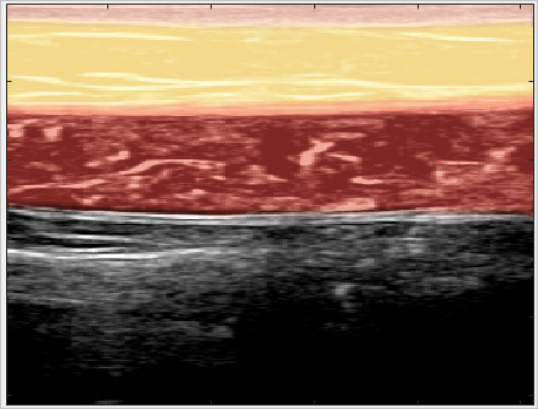

定义 SAT 的直线上边界(皮肤—脂肪层)和二次曲线下边界(脂肪—肌肉层)

从二维规化图像,建立 CNN 回归模型以决定 SAT 的上边界和下边界

皮下脂肪含量(Subcutaneous Adipose Tissue,SAT)是体脂肪测试的重要指标, 而腹部 SAT 的厚度对于健康和体能有重大影响